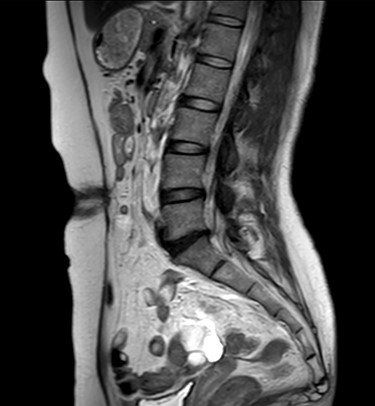

A 47-year-old woman was referred to us by her obstetrician. She developed a PHS after laparoscopic total hysterectomy with right oophorectomy performed 3 years previously. She reported pain with intermittent bulging on the superior aspect of the umbilical region. Clinical examination revealed a single hernia orifice at that location. Her height was 161.1 cm, with a weight of 60.1 kg, yielding a body mass index of 23.16 kg/m2. Her medical history included uterine fibroids and ovarian cysts. She had no history of smoking. Magnetic resonance imaging (MRI) revealed protrusion of adipose tissue at the upper side of the umbilical region, through a fascial defect measuring 9 × 13 mm; diastasis recti was also noted (Figs 1 and 2).